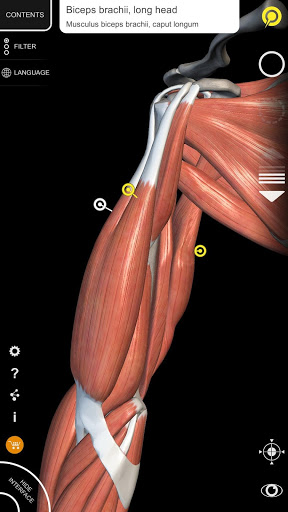

"Anatomy 3D Atlas" memungkinkan Anda mempelajari anatomi manusia dengan cara yang mudah dan interaktif.

Melalui antarmuka yang sederhana dan intuitif, Anda dapat mengamati setiap struktur anatomi dari sudut mana pun.

Model 3D anatomi sangat terperinci dan memiliki tekstur hingga resolusi 4k.

Pembagian berdasarkan wilayah dan tampilan yang telah ditetapkan sebelumnya memudahkan pengamatan dan studi bagian tunggal atau kelompok sistem dan hubungan antara organ yang berbeda.

saraf • Sistem pernapasan • Sistem pencernaan • Sistem urogenital (pria dan wanita) • Sistem endokrin • Sistem limfatik • Sistem mata dan telinga FITUR • Antarmuka yang sederhana dan intuitif • Putar dan perbesar setiap model dalam ruang 3D • Opsi untuk menyembunyikan atau mengisolasi satu atau beberapa model yang dipilih • Filter untuk menyembunyikan atau menampilkan setiap sistem • Fungsi pencarian untuk menemukan setiap bagian anatomi dengan mudah • Fungsi penanda untuk menyimpan tampilan khusus • Rotasi cerdas yang menggerakkan pusat rotasi secara otomatis • Fungsi transparansi • Visualisasi otot melalui tingkat lapisan dari yang superfisial hingga yang terdalam • Dengan memilih model atau pin, istilah anatomi terkait akan muncul • Deskripsi otot: asal, • Tampilkan/ Sembunyikan antarmuka UI (sangat berguna dengan layar kecil) MULTIBAHASA • Istilah anatomi dan antarmuka pengguna tersedia dalam 11 bahasa: Latin, Inggris, Prancis, Jerman, Italia, Portugis, Turki, Rusia, Spanyol, Mandarin, Jepang, dan Korea • Istilah anatomi dapat ditampilkan dalam dua bahasa secara bersamaan PERSYARATAN SISTEM • Android 8.0 atau yang lebih baru, perangkat dengan RAM minimal 3GB Reversi